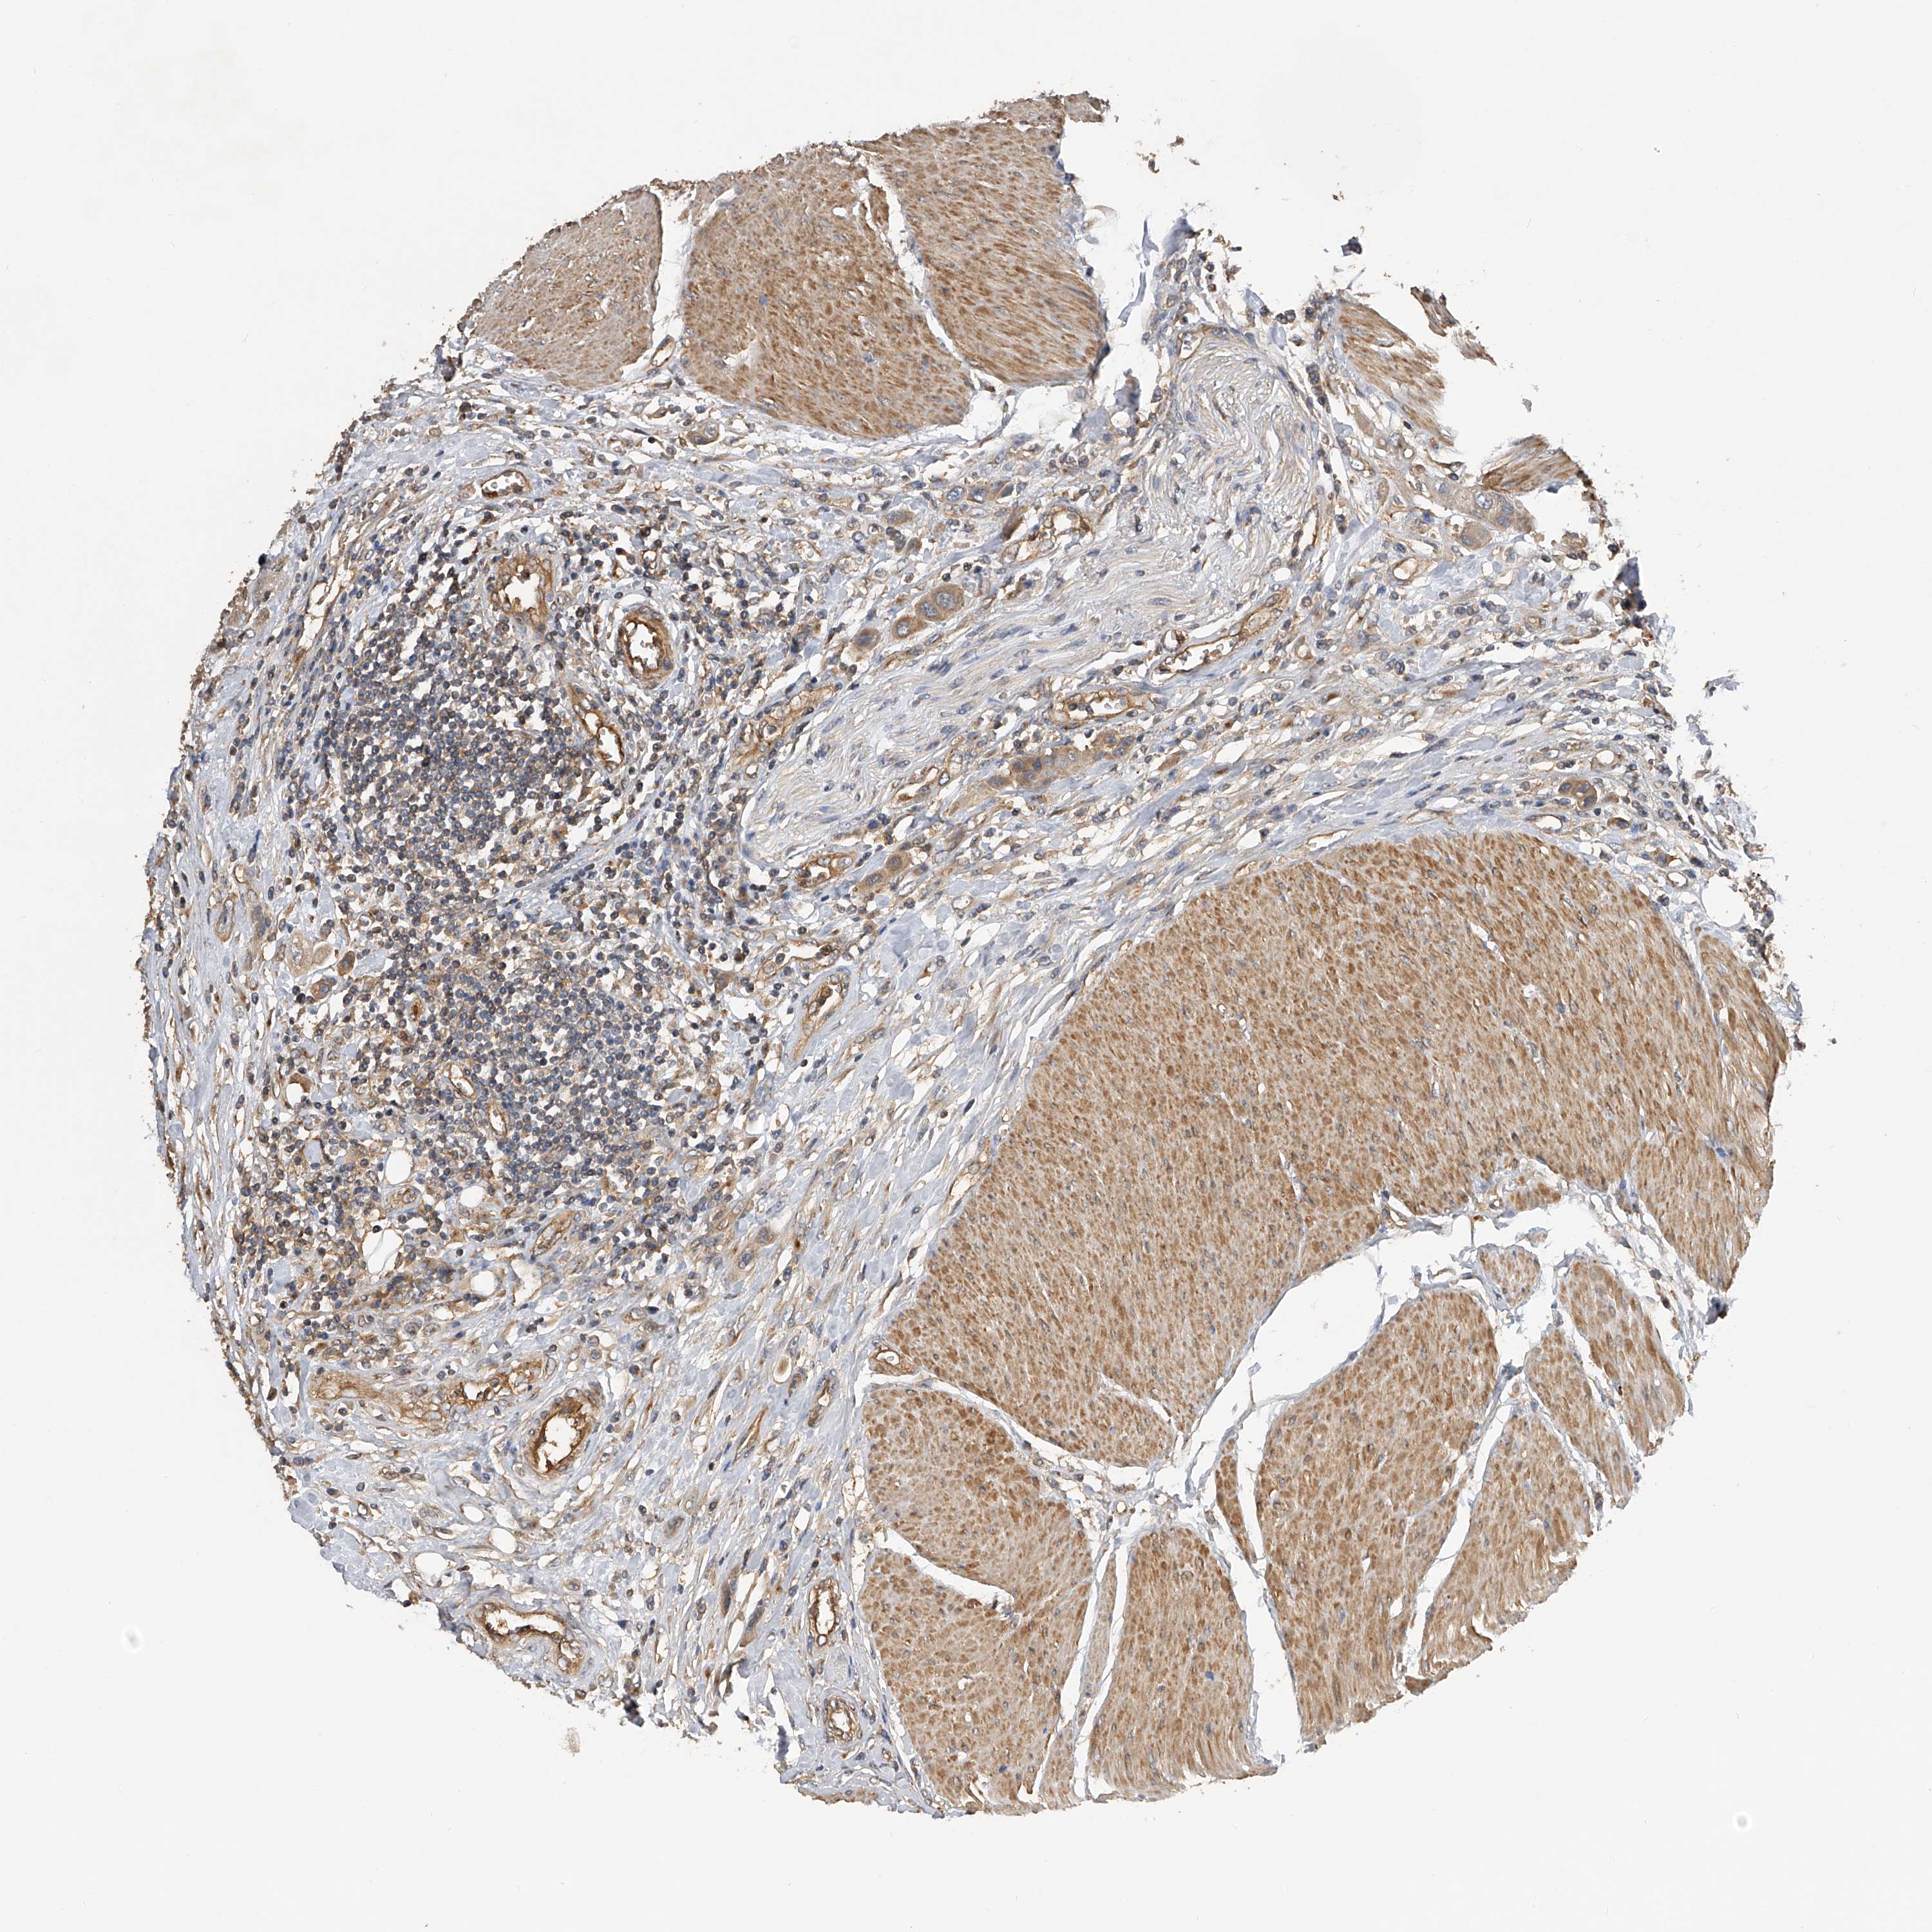

UROTHELIAL CANCER - Protein expressioni

A mouse-over function shows sample information and annotation data. Click on an image to view it in a full screen mode. Samples can be filtered based on level of antibody staining by selecting one or several of the following categories: high, medium, low and not detected. The assay and annotation is described here.

Note that samples used for immunohistochemistry by the Human Protein Atlas do not correspond to samples in the TCGA dataset.

Antibody stainingi

Antibody staining in the annotated cell types in the current human tissue is reported as not detected, low, medium, or high, based on conventional immunohistochemistry profiling in selected tissues. This score is based on the combination of the staining intensity and fraction of stained cells.

Each image is clickable and will lead to virtual microscopy that enables deeper exploration of all samples and also displays staining intensity scores, fraction scores and subcellular localization as well as patient and tissue information for each sample.

Antibody HPA029412

Antibody CAB034366

Staining

High

Medium

Low

Not detected

Intensity

Strong

Moderate

Weak

Negative

Quantity

>75%

75%-25%

<25%

None

Location

Nuclear

Cytoplasmic/membranous

Cytoplasmic/membranous,nuclear

Urothelial carcinoma, Low grade

Urothelial carcinoma, High grade